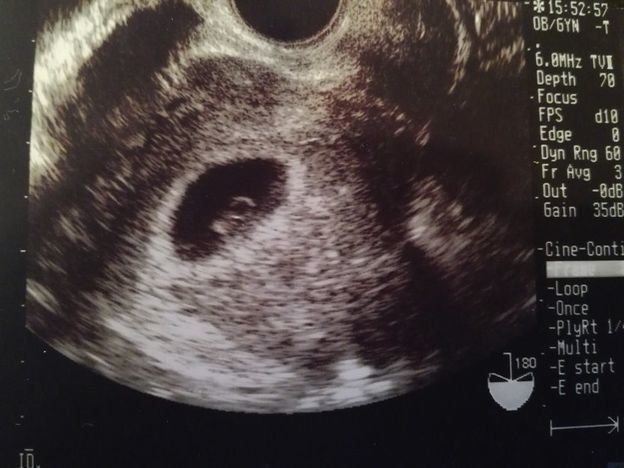

Tomomiさんの妊娠6週目のエコー写真 心拍確認できました

「ちゃんと大きくなっているかな?胎嚢の中に赤ちゃんは見えるかな?」不安な気持ちで内診台へ上がり、思わず手を組んで祈ってしまいました。先生のとっても嬉しそうな「おー、いたいた」という声にほっと胸を撫で下ろし、ピコピコ動くベビちゃん(胎児ネーム)の心拍を見ながら、「現実なのかな?」と信じられない気持ちでいっぱいでした。

私にとって4度目の妊娠陽性反応、そして初めての心拍確認!1つの大きな壁を乗り越えたと同時に、妊娠が継続するのかと、不安な気持ちと闘う日々も続くのでした…。